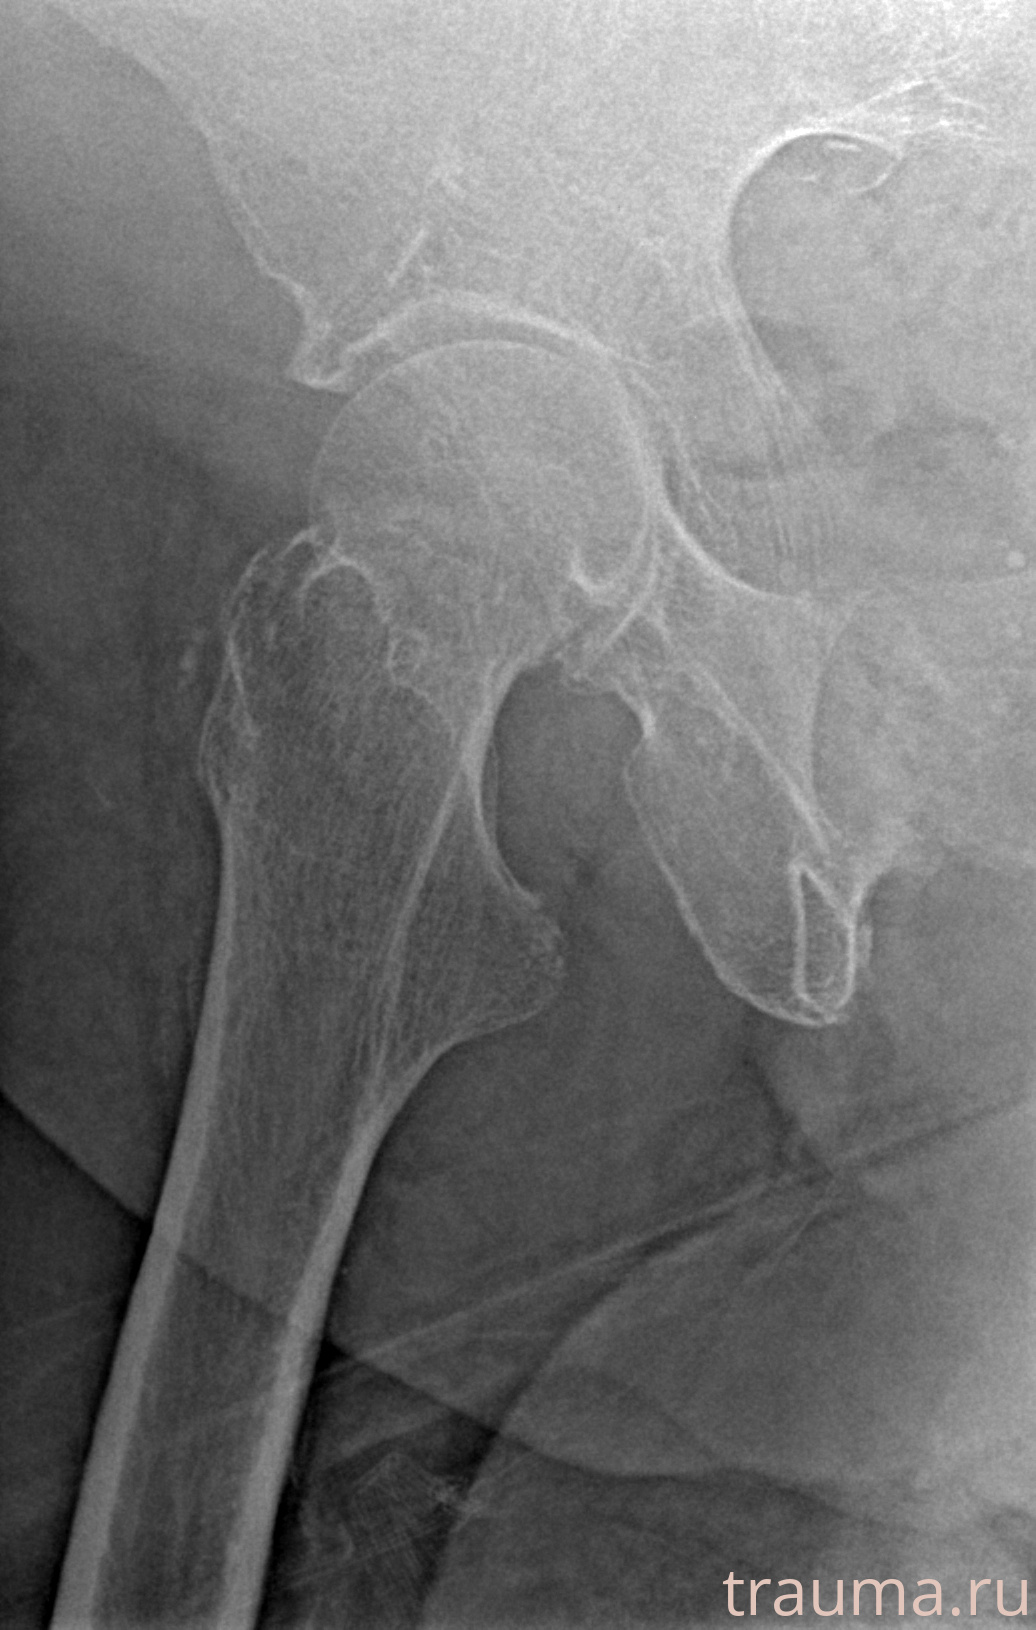

Первая помощь при переломе шейки бедра

Рентген на дому: по вашему адресу приезжает врач-рентгенолог, травматолог-ортопед с мобильным рентгеновским аппаратом, проводит диагностику травмы или заболевания, делает необходимые рентгенограммы, дает рекомендации по дальнейшему лечению. Получить качественные снимки в домашних условиях возможно благодаря уникальной методике, разработанной МосРентген Центром для института  Склифосовского